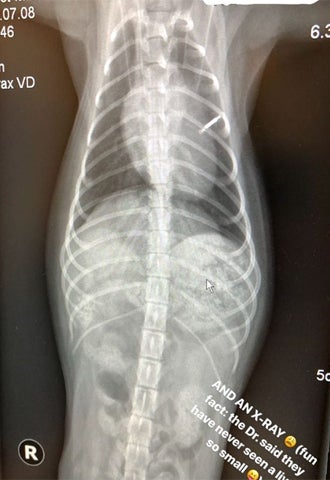

Die Assistentin setzte sofort zur Herzmassage an, führte diese minutenlang aus. Und plötzlich regte sich Nugget wieder! Danach ging es für das kleine Haustier ab zum Tierarzt. Bei der Tierärztin Usha Patel in der Praxis Schwarzspanierhof wurde Nugget geröntgt und bekam eine Infusion. Jetzt ist der kleine Pudel wieder wohlauf!